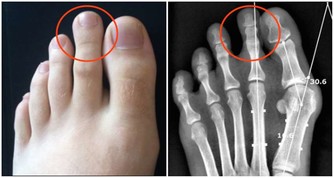

5.久坐:長期上網屬於靜態性動作,血液粘稠度較高,下肢可能形成深靜脈血栓,

運動時血栓脫落,可能會造成肺梗塞,嚴重可能導致猝死。